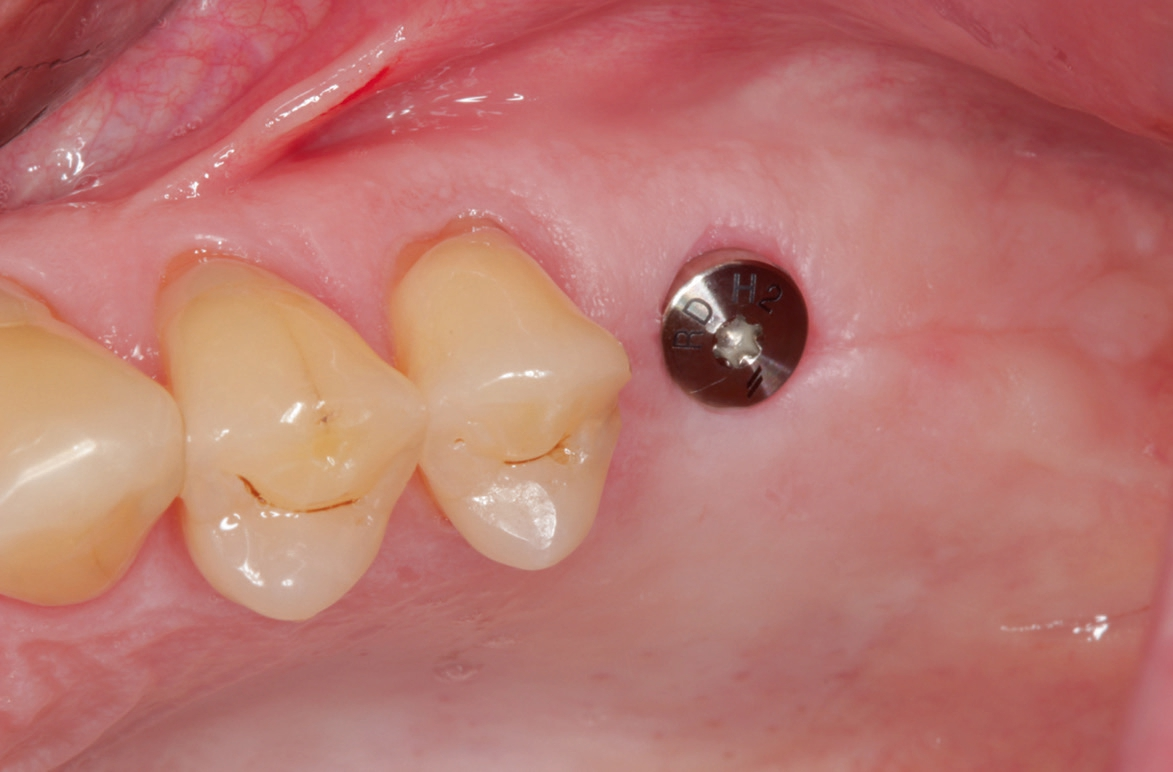

Nach lokaler Anästhesie wurden ein Kieferkammschnitt und eine nur minimale Mobilisation des Mucoperiostlappens durchgeführt. Beim internen Sinuslift nach Summers wird die Pilotbohrung bis ca. 1 mm vor die Begrenzung der Kieferhöhle vorgenommen und je nach Knochenangebot und Qualität mittels verschiedener Osteotome (Institut Straumann) weiter aufbereitet. Unabdingbar ist dabei die regelmäßige Kontrolle der Unversehrtheit der Schneider‘schen Membran durch einen „Nasenblasversuch“. Nach erfolgreicher Aufbereitung des Lagers konnte ein Implantat Größe 4,1/10 mm sehr gut primärstabil inseriert werden, anschließend primärer Wundverschluss mittels 5/0 monophiler Naht. Nach vier Monaten erfolgte die minimalinvasive Freilegung und Applikation des Gingivaformers.

Die Übertragung der Implantatposition ins zahntechnische Laboratorium wird mittels offener Abformung mit individuellem Löffel und einem stabilen Polyäthermaterial vorgenommen. Die achsgerechte Position des Implantates ermöglichte die Anfertigung einer transocclusal verschraubten, verblendeten Zirkonoxidkrone auf einer Klebebasis. Die Besonderheit der Konstruktion ist dabei, dass das Metall der Klebebasis bei der fertigen Konstruktion komplett von Zirkon umschlossen ist. Dies erfordert eine hohe technische Präzision und eine spezielle „Verklebehilfe“ im Labor. Zur ersten Einprobe der Krone beim Patienten befestigen wir die Krone zunächst nur provisorisch auf der Klebebasis. Dies stellt sicher, dass sie bei eventuell notwendigen Korrekturen leicht gelöst und erneut gebrannt werden kann. Ist die Krone in Farbe und Form fertig gestellt, so muss sichergestellt sein, dass die endgültige Verklebung exakt in der gleichen Position auf der Klebebasis erfolgt, wie die zuvor einprobierte. Dafür fertigen wir einen Kunststoffschlüssel.